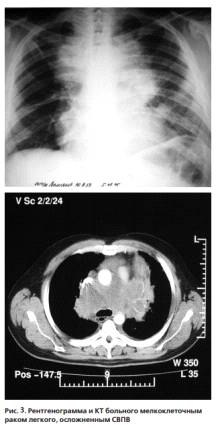

потенциально излечимыми заболеваниями, такими как мелкоклеточный рак лёгкого,

неходжкинские лимфомы и герминогенные опухоли. Интересно отметить, что наличие

СВПВ в некоторых исследованиях являлось благоприятным прогностическим фактором

для мелкоклеточного рака легкого и неблагоприятным для немелкоклеточного рака